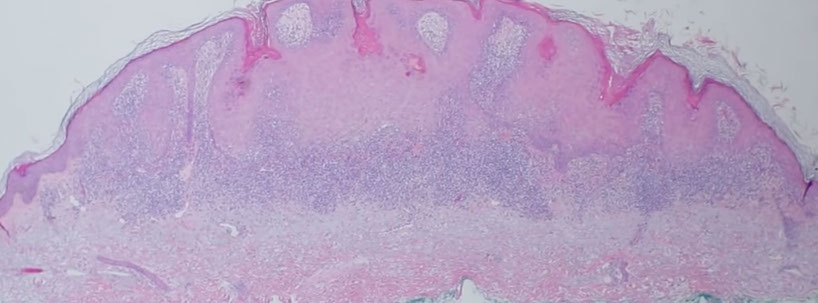

Syringocystadenoma Papilliferum (SCAP)

aka papillary syringadenoma

b9 sweat gland proliferation that arises in the middle of a nevus sebaceus

- warty tumor of scalp, neck, and face that can occur at any age

- clinically is a slow growing or recent change in a brithmark, may be crusty and start to bleed

- 1/3 have adjacent nevus sebaceus, 10% with adjacent BCC

- malignant counterpart is syringocystadenocarcinoma papilliferum

Micro: glandular papillary prolif connected to skin surface

- has ducts that look similar to sweat ducts sometimes, which are lined by cuboidal cells, that eventually empty to skin surface

- dense plasma cell infiltrate in the dermis, or in the middle of the papillary structures